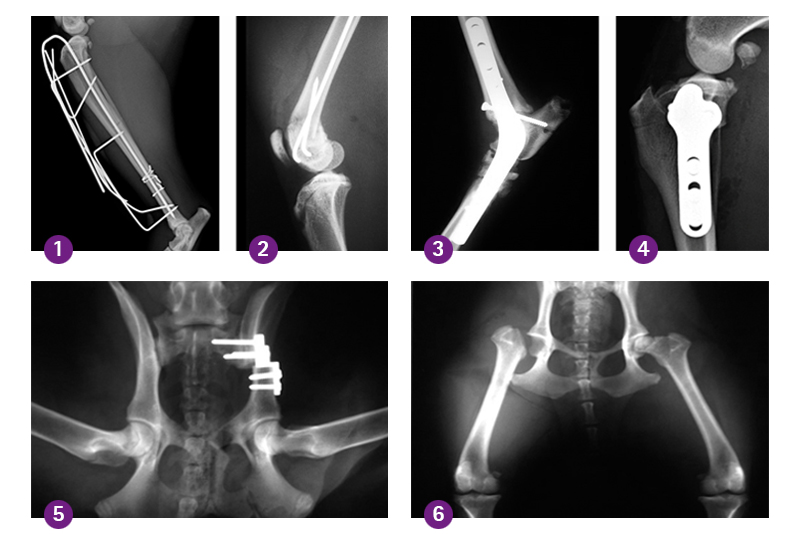

(1) Tibiafraktur mit Fixateur externe (2) Supracondyläre Femurfraktur (3) Pantarsale Arthrodese (4) TPLO (5) TPO (6) FKHR